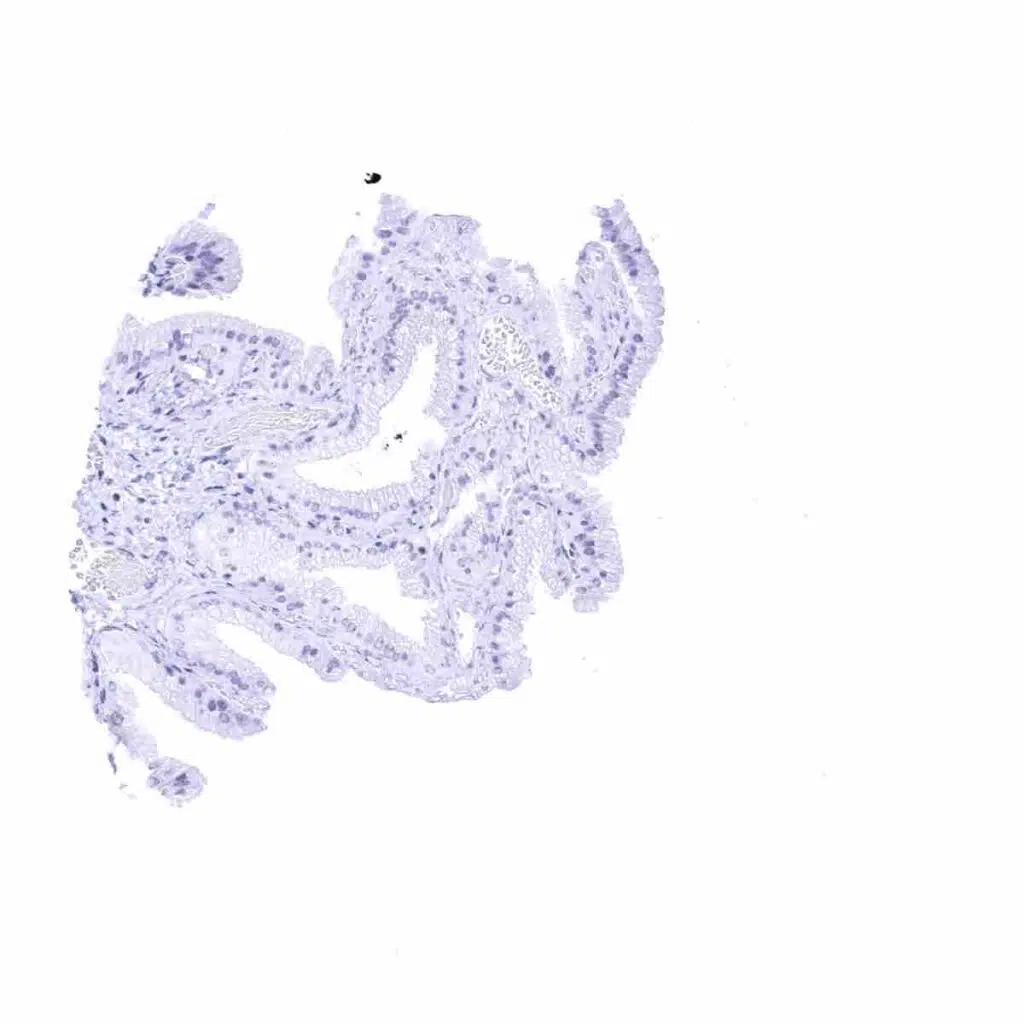

Fallopian tube, mucosa